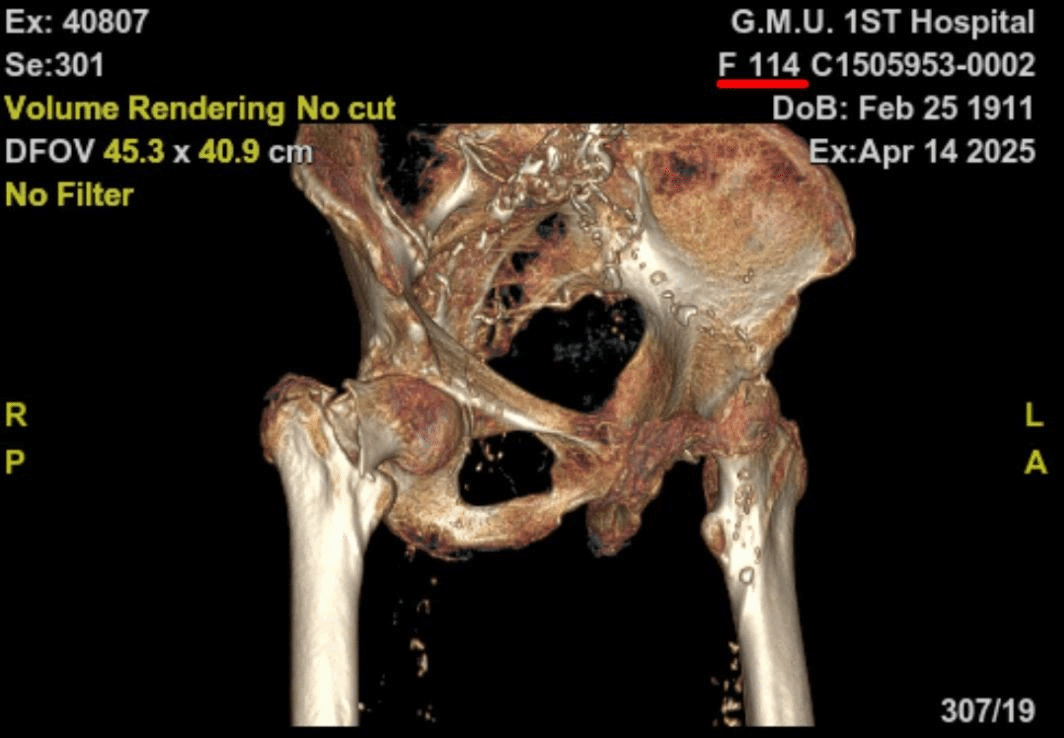

术前全面评估,患者术前有下肢DVT、肺部感染、慢性心功能不全、中度贫血、低蛋白血症,X线片显示股骨皮质极薄、股骨髓腔呈“烟筒样”改变。术前多学科会诊并给予抗凝、控制肺部感染、改善贫血和低蛋白血症、治疗骨质疏松、改善心功能,为麻醉、手术治疗创造条件。

经过精心术前准备,患者各项指标明显改善,考虑到患者骨质疏松非常严重和早期下地活动的要求,经多学科讨论,并且与家属充分沟通和慎重考虑,卢伟杰团队最终决定采用水泥型人工股骨头置换术进行治疗。